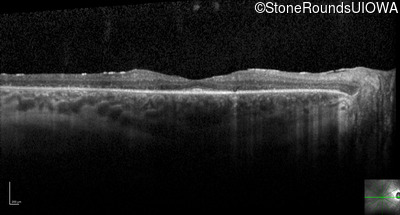

Optical Coherence Tomography - Left - 20/50

Exemplar / OCT Stack

OCT Stack